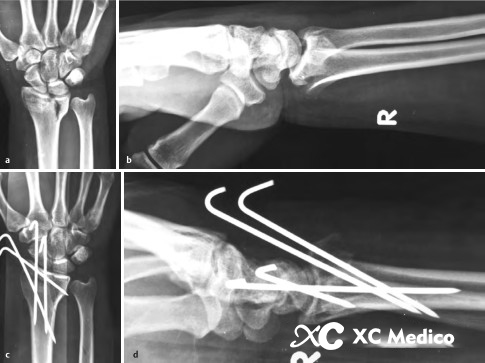

2. В технике Капанджи в место перелома вставлено от двух до трех K-проводов, чтобы уменьшить и исправить дистальные фрагменты перелома в желаемое положение. После уменьшения k-проволоки продвигаются в проксимальные фрагменты (рисунки AF ниже).